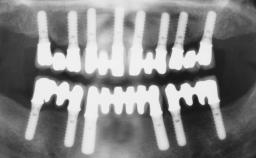

Iliac-Crest Block for Vertical and Horizontal Space Filling in the Anterior Maxilla

A 31-year-old man presented to our clinic 30 days after a motor vehicle accident in which he had suffered a dentoalveolar fracture in the anterior maxilla, including avulsion of teeth 12 and 11 and luxation of tooth 21. He was first treated on the night of the accident in a small city hospital with no oral and maxillofacial surgeon on the staff. A wired retention had been applied and the teeth repositioned to the best of the clinicians’ abilities. When he first presented to our care, the patient showed extrusion of teeth 12 and 11 associated with gingival recession due to bone loss in the anterior maxilla, and the stainless steel wires were still present.

Bone Augmentation Horizontal|Staged|Vertical

Augmentation Materials Autogenous chips|Autogenous block(s)